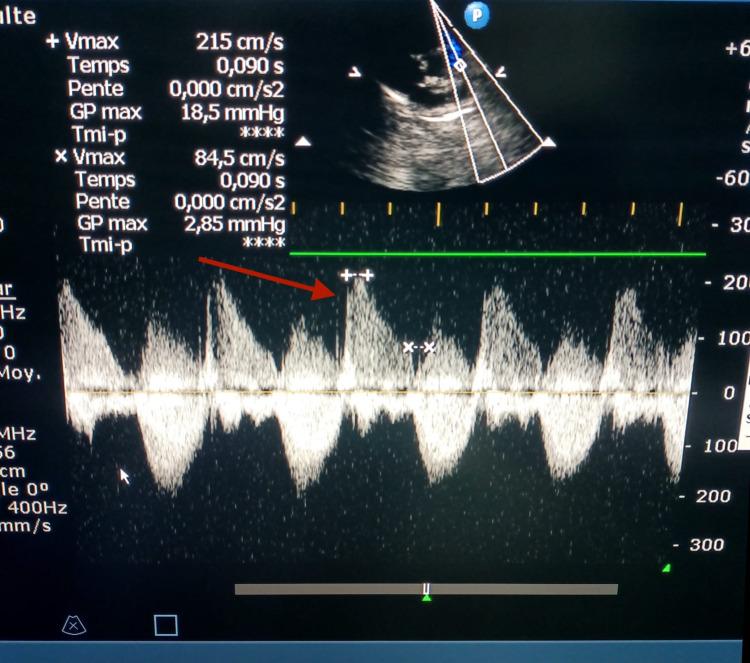

背景 法洛四联症(TOF)是最常见的青紫型先天性心脏病。TOF的手术方法不断发展,现在许多中心倾向于对TOF进行早期修复。本研究旨在确定术后并发症的发生率,如肺动脉瓣关闭不全、残余肺动脉狭窄和室间隔交通。方法 我们进行了一项横断面观察性研究,以描述性和分析性为重点,纳入了61例接受TOF手术的患者。结果 总共,39例(63.9%)患者为典型TOF,22例(36.1%)为非典型TOF。在我们的研究中,32例(56.14%)患者有肺动脉瓣关闭不全,其中20例有轻度肺动脉瓣关闭不全(占肺动脉瓣关闭不全病例的62.5%),右心室流出道扩大的患者中有79.4%有肺动脉瓣关闭不全(p<0.005)。在没有右心室流出道扩大的患者中,发现3例肺动脉瓣关闭不全,发生率为16.6%。6例(10.52%)患者有残余肺动脉狭窄。此外,本研究中发现2例(3.2%)轻度残余室间隔缺损病例。结论 TOF治疗的术后并发症很常见,患者一生都需要医疗护理。

https://cdn.ncbi.nlm.nih.gov/pmc/blobs/8148/9167490/bb34aa18182e/cureus-0014-00000024773-i04.jpg

https://cdn.ncbi.nlm.nih.gov/pmc/blobs/8148/9167490/327bd06c1e5c/cureus-0014-00000024773-i01.jpg

https://cdn.ncbi.nlm.nih.gov/pmc/blobs/8148/9167490/716c22335949/cureus-0014-00000024773-i02.jpg

https://cdn.ncbi.nlm.nih.gov/pmc/blobs/8148/9167490/7237676dcedd/cureus-0014-00000024773-i03.jpg